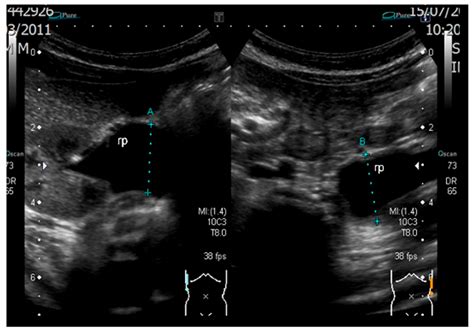

Pyelectasis of the fetus is typically diagnosed during routine prenatal ultrasound examinations. The diagnosis is based on the measurement of the anteroposterior diameter (APD) of the renal pelvis. The severity of pyelectasis is categorized as follows:

• Fetal MRI: This can provide more detailed images of the fetal kidneys and urinary tract.

• Postnatal ultrasound: After birth, a follow-up ultrasound can help assess the condition of the kidneys and urinary tract.